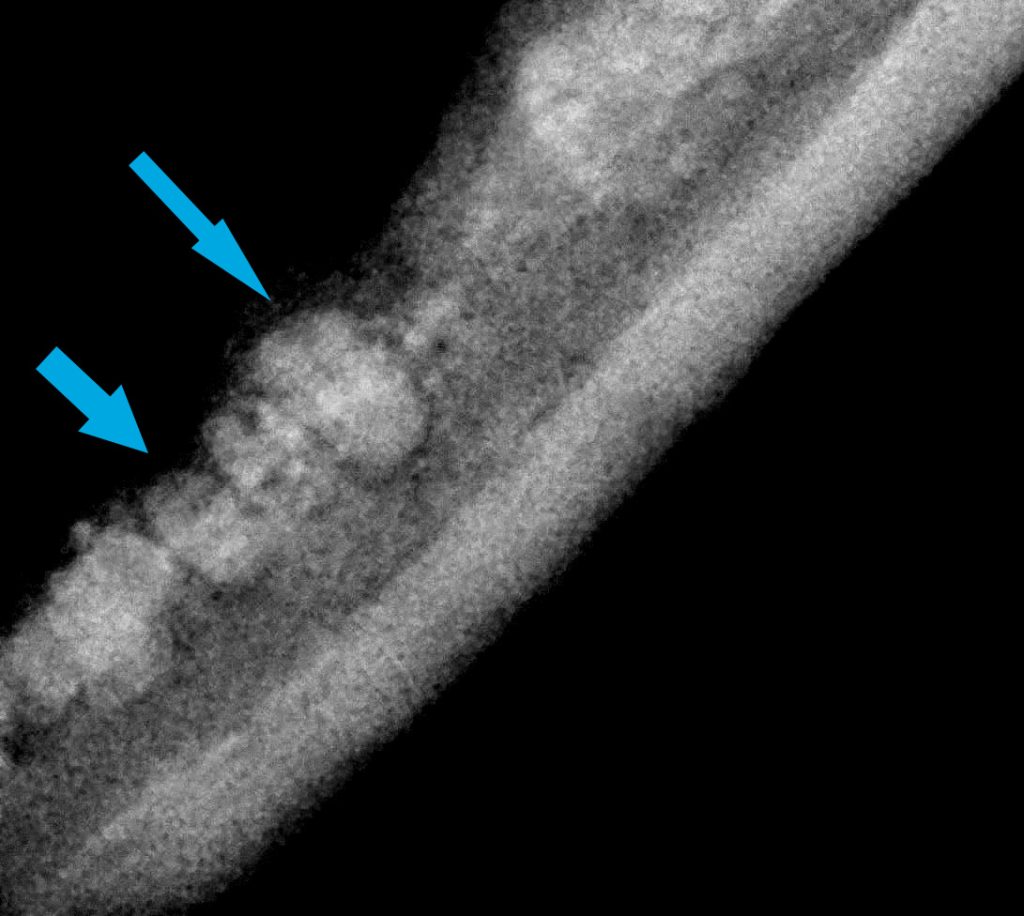

ESTUDIO RADIOLÓGICO DENTAL

El estudio radiológico dental correspondiente desveló la presencia de restos radiculares de los dientes 207 302, 308, 404, 408, 409 (incisivo, premolares y colmillo).

-Al ser la GECF una enfermedad idiopática de origen inmunomediado es imprescindible que no queden restos radiculares en la cirugía de exodoncias para evitar así el estímulo antigénico que mantenga la inflamación y el dolor en el paciente.

-Dado el escaso tamaño de los dientes del gato, sin la técnica ni el equipamiento adecuado, es relativamente sencillo dejar algún resto radicular (en ocasiones de forma desapercibida). El fresado «a ciegas» de un posible resto radicular, además de que está contraindicado por sus posibles complicaciones asociadas, no soluciona el problema de que queden restos radiculares.